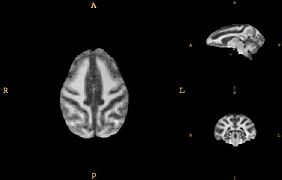

• Develop a juvenile WM/GM/CSF atlas from normal subject images.

• The atlas construction procedure was adapted from Automatic brain segmentation in rhesus monkeys; M. Styner, R. Knickmeyer, S. Joshi, C. Coe, S. J. Short, and J. Gilmore. Proc SPIE Vol 6512 Medical Imaging 2007, pp 65122L-1 - 65122L-8.

Images